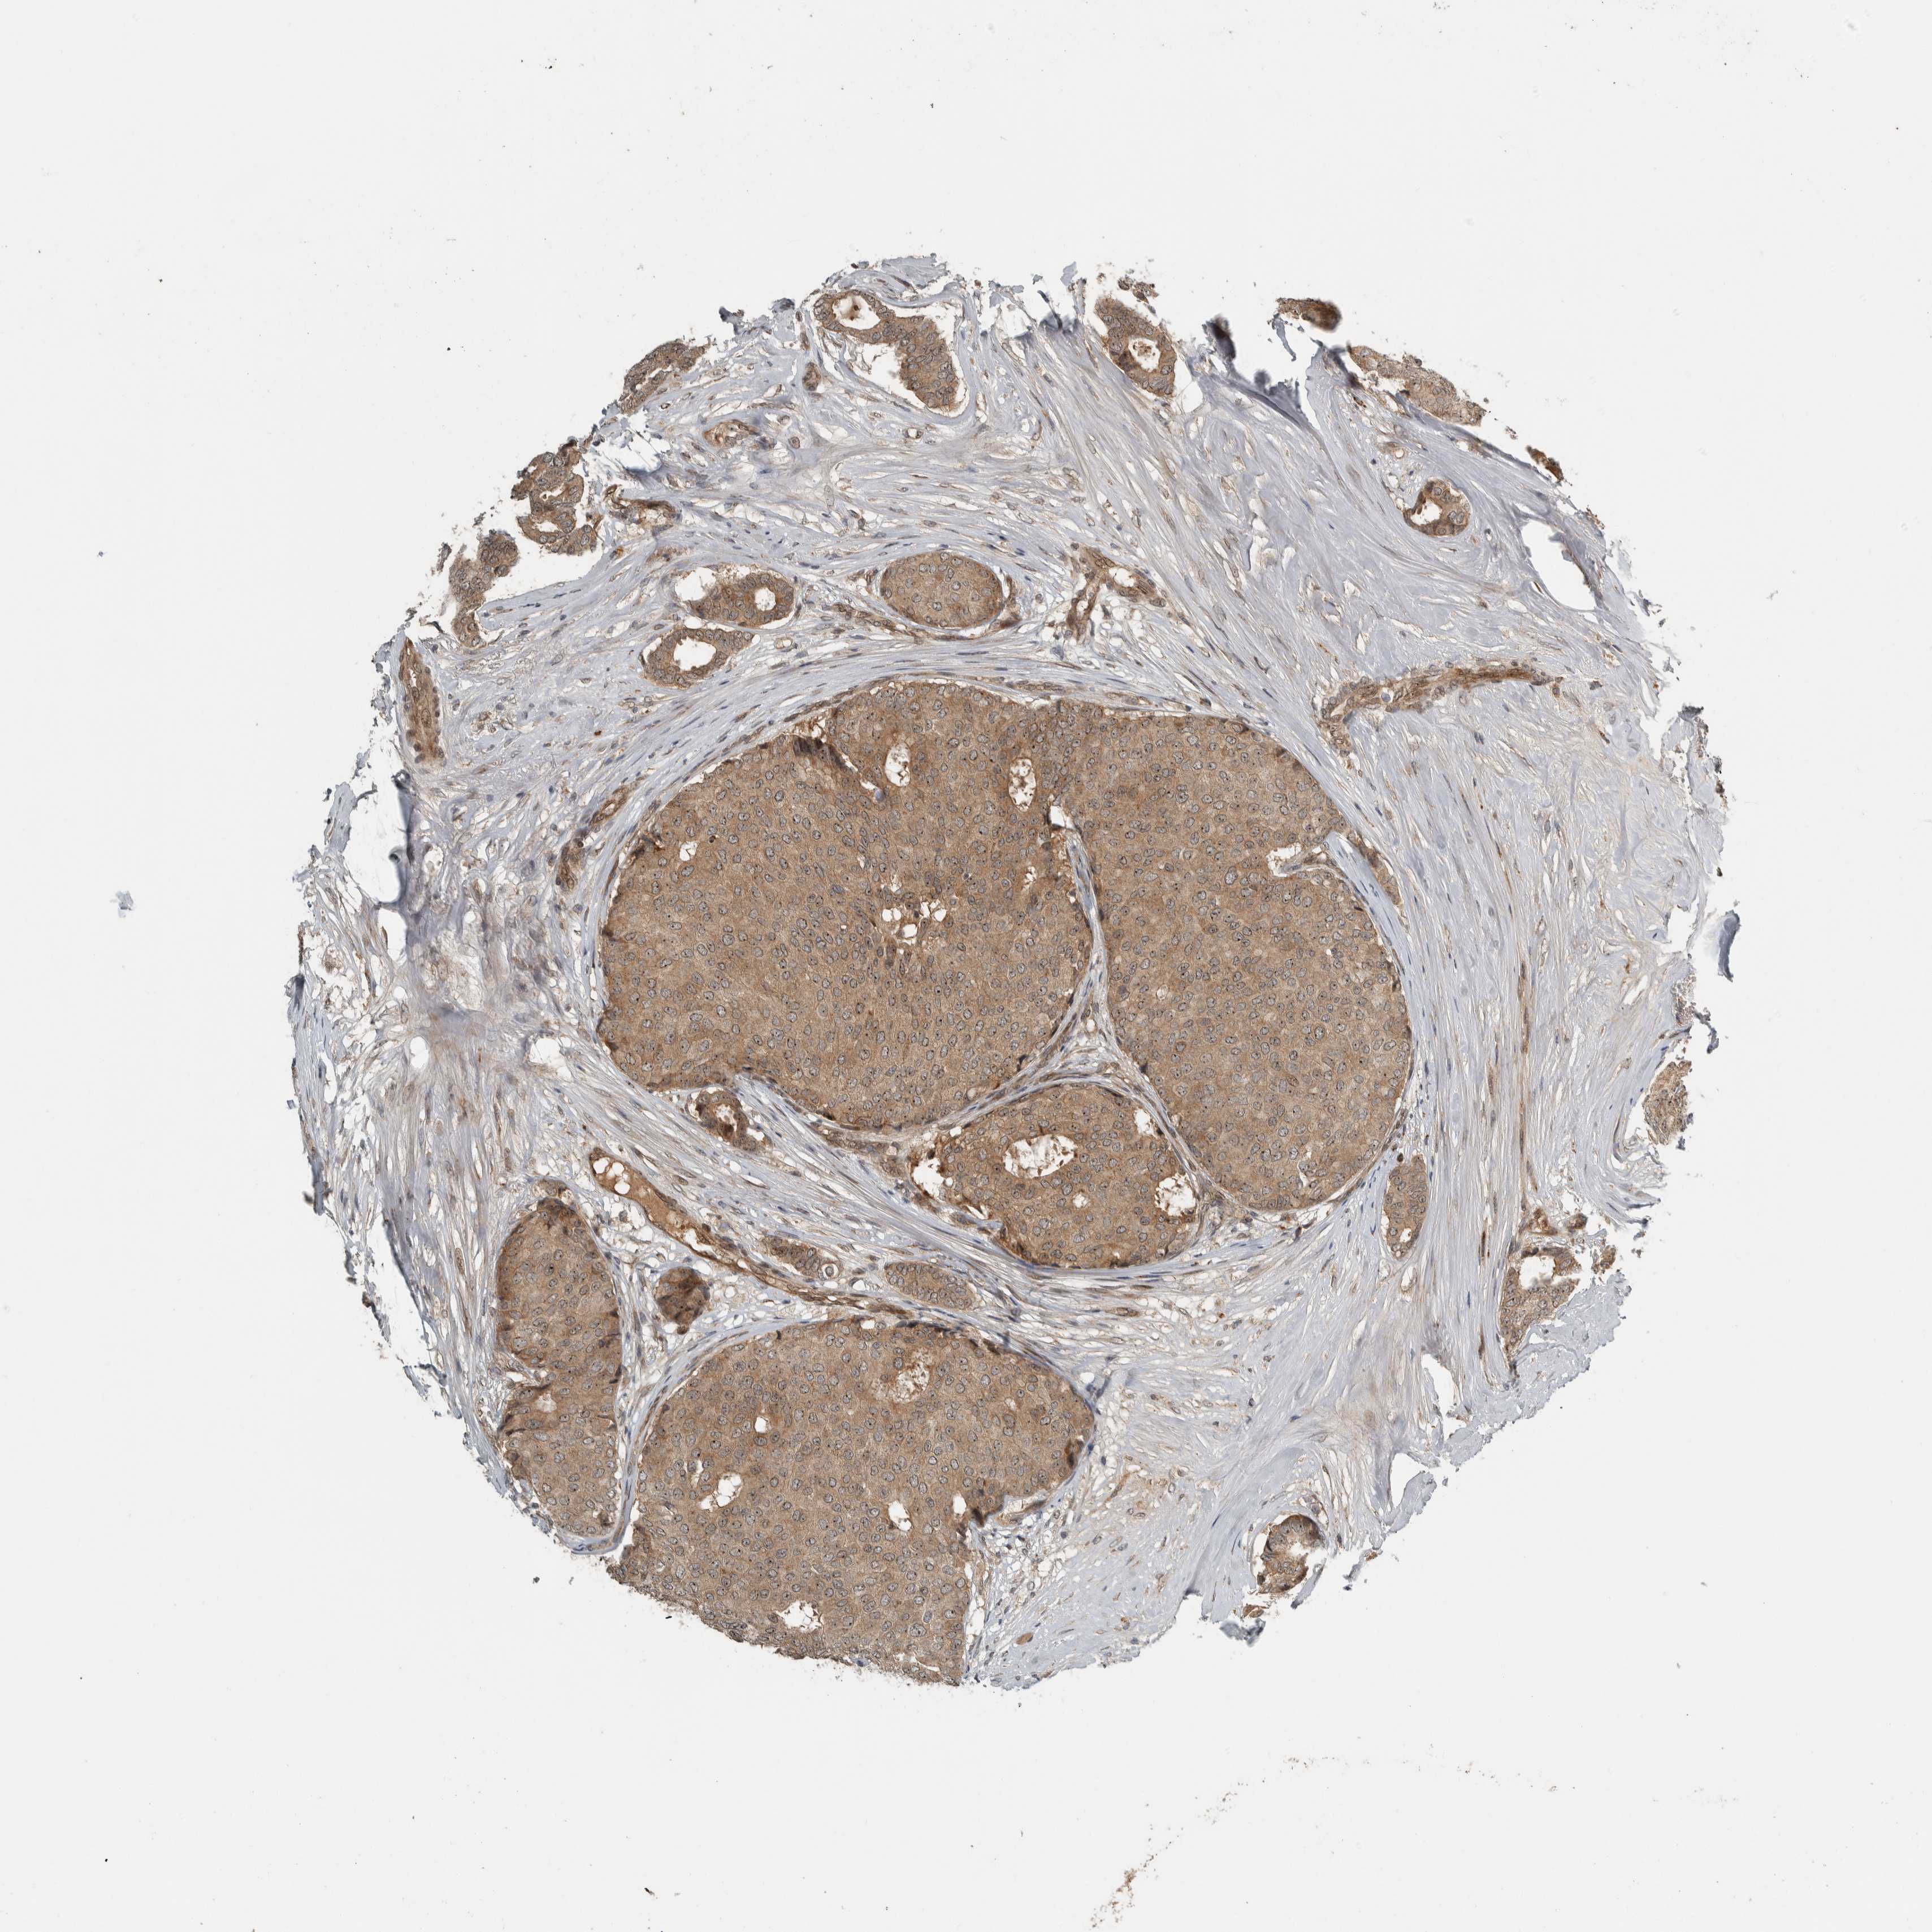

CANCER BREAST CANCER Show tissue menu

BRCA TCGA BRCA VALIDATION PROTEIN EXPRESSION